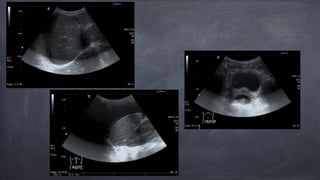

Traitement chirurgical pourRUPTURE INTRAPÉRITONÉALE très rares cas de Tx conservateur haut risque d’ascite urinaire, urémie, acidose Exploration et réparation, via sutures résorbables en continu Cathéter Foley aussi laissé en place qq jours • Cystographie de contrôle

• 36.

• Cystographie denotre patiente • J#3 post-op